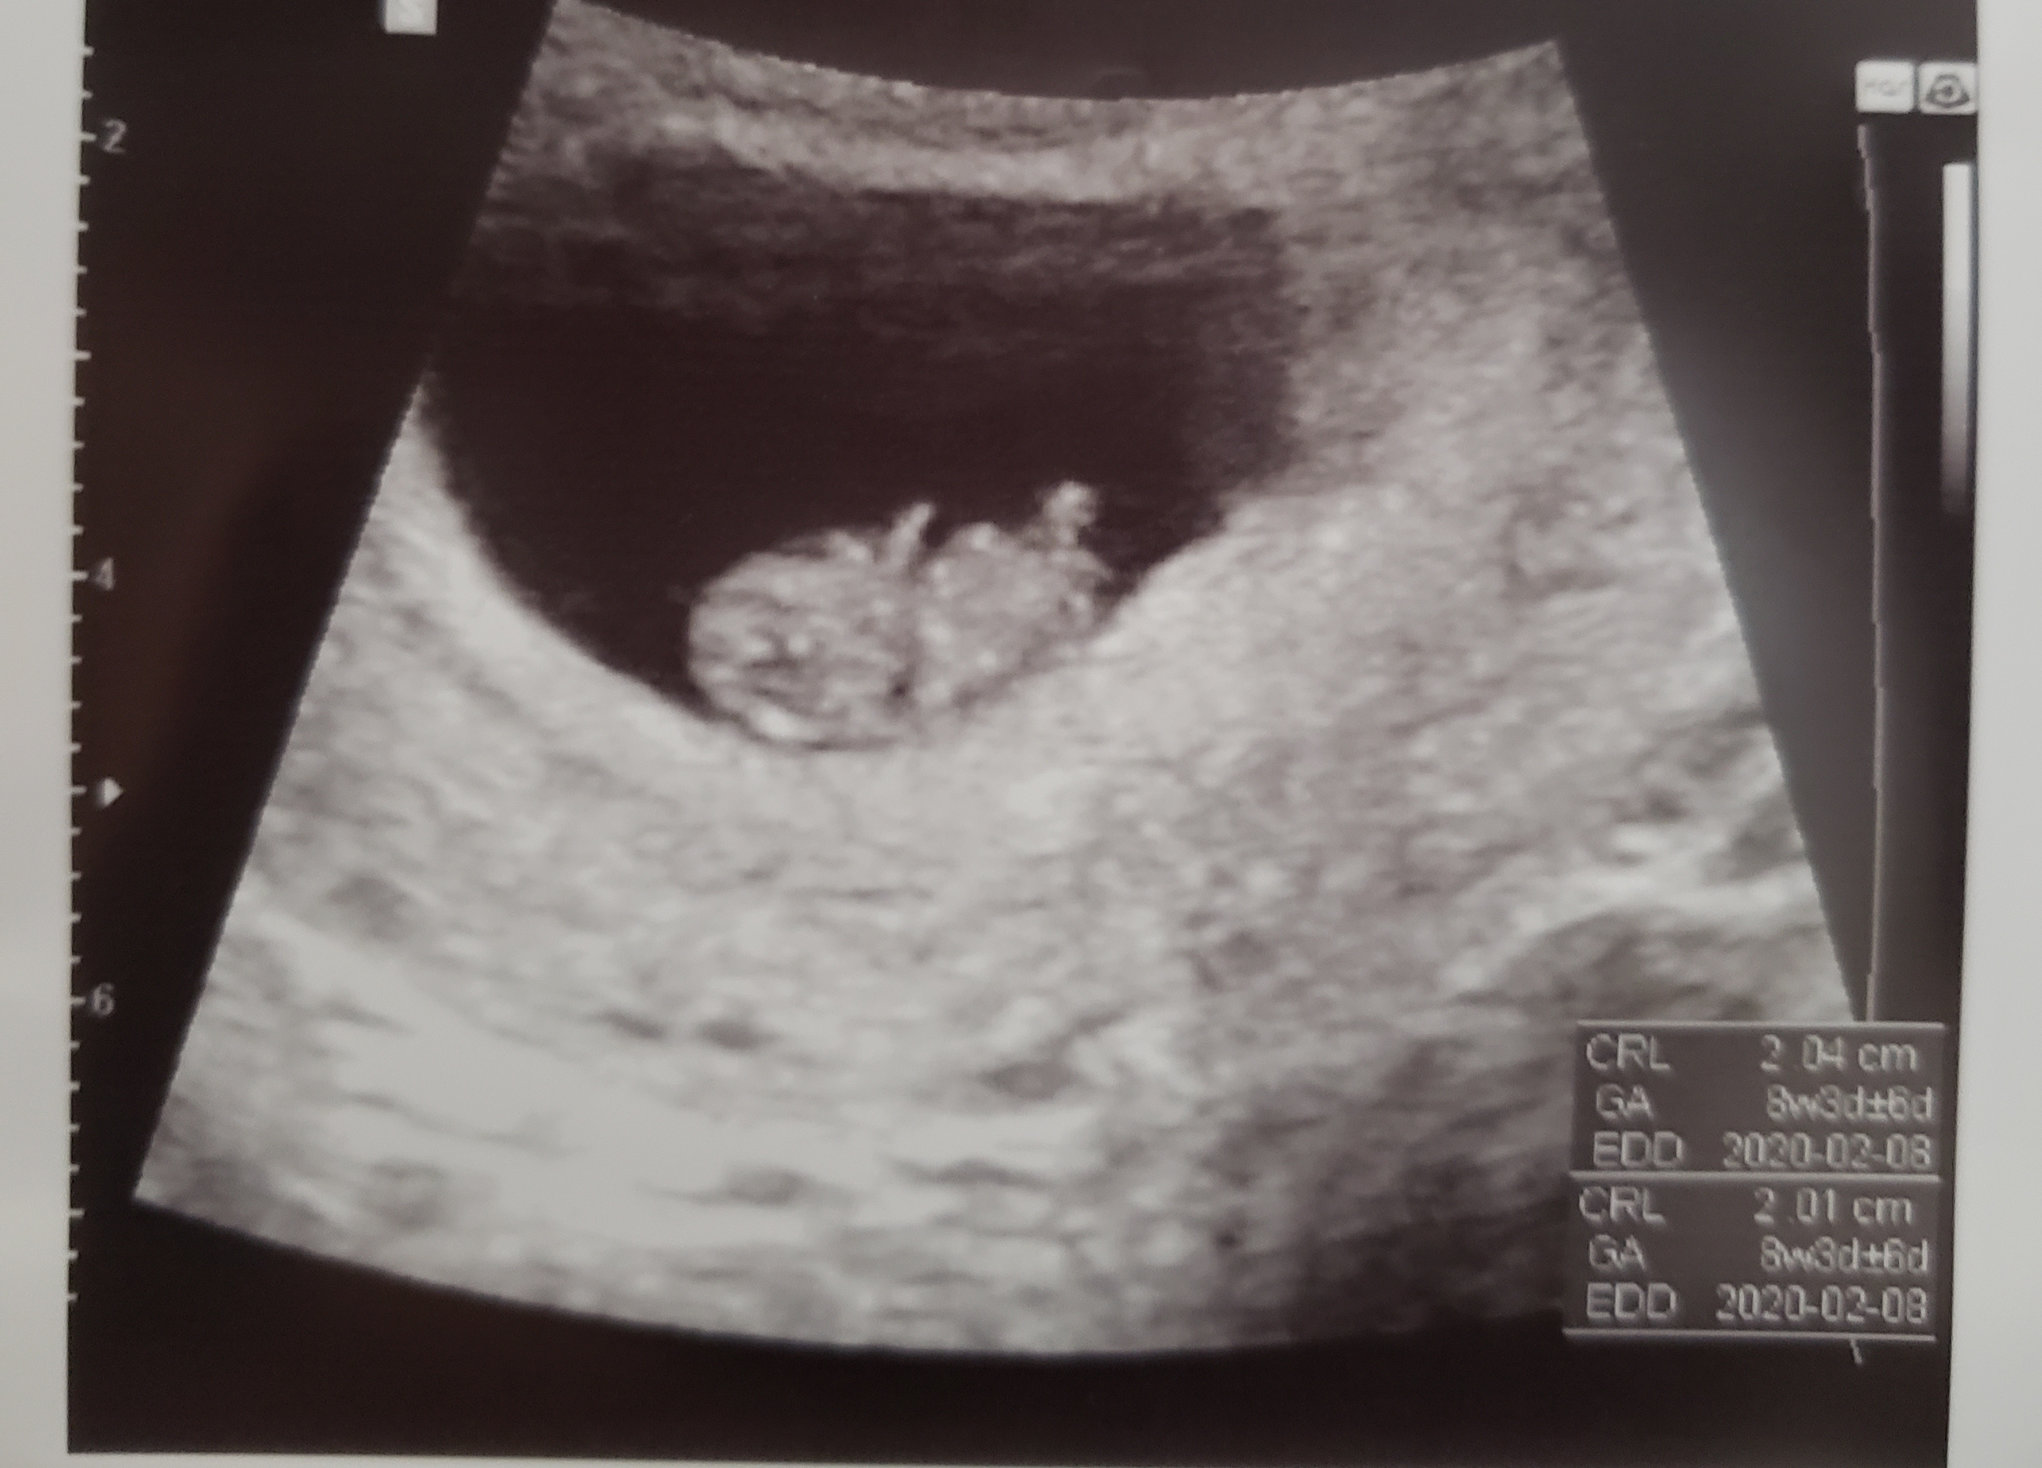

Well, we’ve got two! Heartbeats 115 and 118, NP is happy with those heart rates and says they typically like to see ~100 around 6 weeks. So if they're happy I’m happy I’m 6w5d.